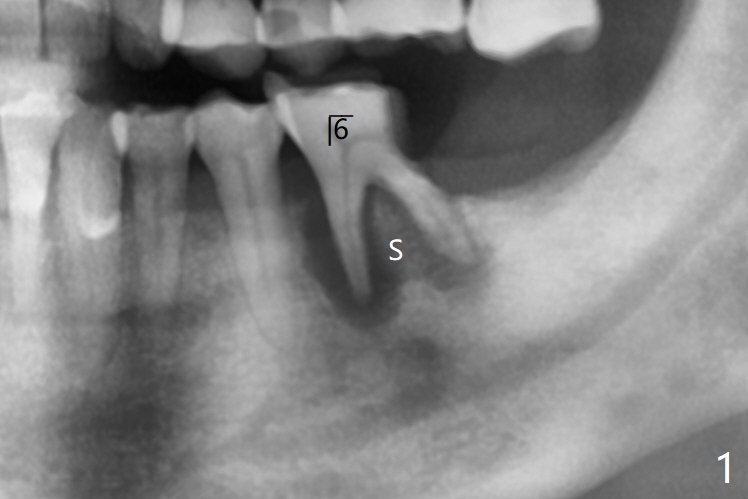

66岁男要求拔除左下6(图一),中隔好像斜型吸收(S),如果即刻植牙植入中隔,冠方螺纹三面暴露(图二:箭头)。当植入近中牙槽窝(图三:M),似乎只有一面螺纹暴露。病人右下3,4颊侧骨板仿佛植骨后修复,不妨尝试同样方法。不过需要如下改善:尽量少制备粘性骨块,用剩余PRF上清液临时调袢骨粉,放置牙槽窝底部(好压紧),而粘性骨块放在颊侧缺陷和牙槽窝开口(防止下面骨粉脱落),最后放置PRF膜。安置间隙维持器,拍摄根尖片,放置牙周敷料(避免缝线)。